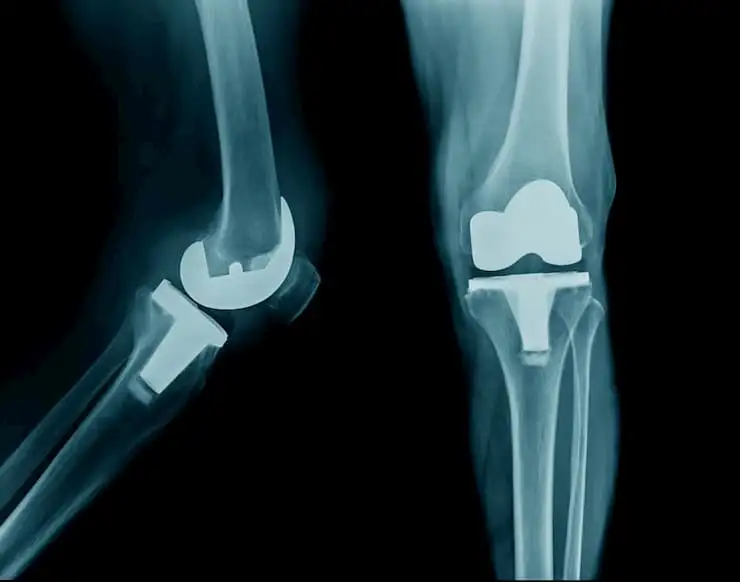

Эффективность сочетанного применения дулоксетина для приема внутрь и внутрисуставных инъекций при остеоартрозе коленного сустава

Было проведено проспективное рандомизированное открытое исследование для определения полезности комбинации дулоксетина и инъекций гиалуроновой кислоты (ГК) и кортикостероидов (КС) при остеоартрозе коленного сустава.

У пациентов с остеоартрозом коленного сустава прием дулоксетина наряду с внутрисуставным введением кортикостероида в сочетании с гиалуроновой кислотой эффективно облегчает боль и улучшает функцию коленного сустава.